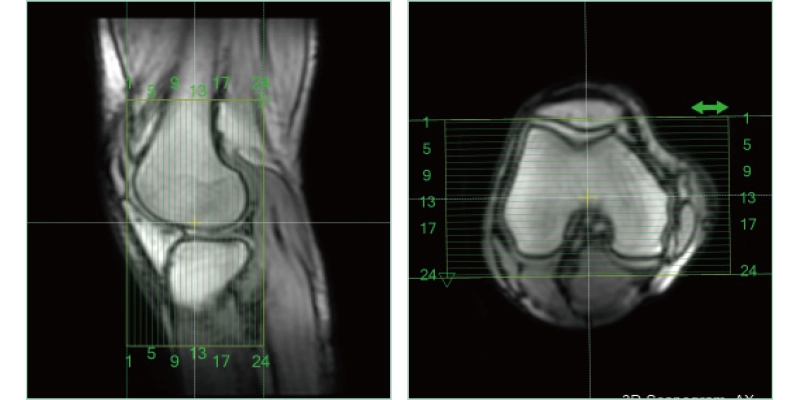

AutoPose Knee

The slice line setting support function, "AutoPose," automatically sets the slice lines as soon as the scanogram is scanned.